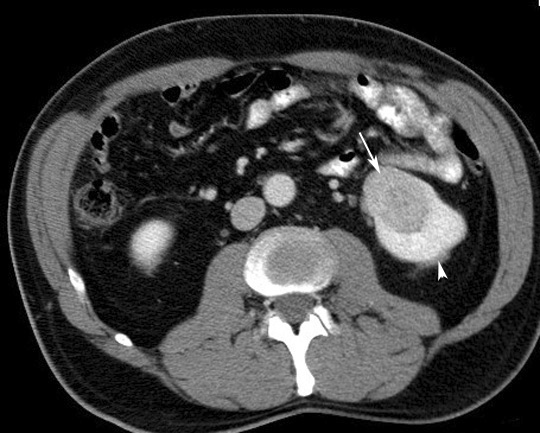

CT scan in another patient with Renal Cell Carcinoma

• Mass is cystic and solid.

• Tumor nodules are seen arising from the wall of the cyst.